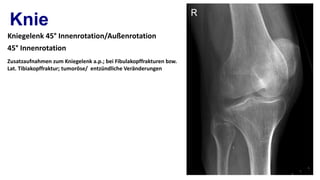

Das Leitbild der „Speziellen Unfallchirurgie“ basiert auf dem Leitbild für das Fach „Orthopädie und Unfallchirurgie“: „Orthopädie und Unfallchirurgie umfasst die Vorbeugung, Erkennung, konservative und operative Behandlung, Nachsorge und Rehabilitation von Verletzungen aller Art und deren Folgen sowie von angeborenen und .Digitales Röntgen des gesamten Bewegungsapparates.sehr freundlich, mit Röntgen, Diagnose und Gespräch in einer Stunde fertig – perfekt.Spezielle Unfallchirurgie Alles in einem Buch: Kompakte und herstellerunabhängige Darstellung der Speziellen Unfallchirurgie.Diagnostik! Die Röntgen-Technik wurde stetig weiterent wickelt und die Strahlendosis immer weiter reduziert: Nach den ersten einfachen Röntgenaufnahmen und der Durchleuchtung unmittelbar am Leuchtschirm wurde die Film-Folien-Technik entwickelt, die trotz geringerer Dosis ein deutlicheres und speicherfähiges Bild ermöglicht. Zur Diagnose nutzen . und laterale Röntgenaufnahme des Knies mit proximaler Tibia beinhalten.